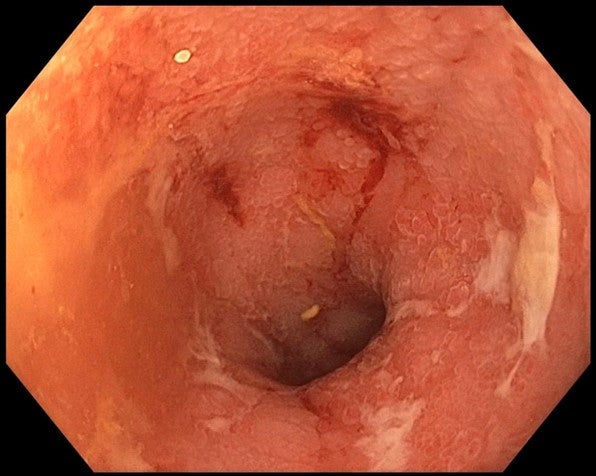

Pro tento stav byly nasazeny systémové kortikosteroidy v adekvátní dávce s velmi pozvolnou detrakcí, avšak klinicky došlo jen k částečné remisi počtu stolice (8–10 denně), přetrvávaly úporné tenesmy a urgence. Endoskopická kontrola do 4 týdnů po zahájení kortikosteroidů neprokázala známky remise, v rektu byl nález eMayo 3 s plošnými vředy po celé cirkumferenci (obrázek č. 1).

Obrázek č 1 – floridní zánětlivé změny, eMayo 3